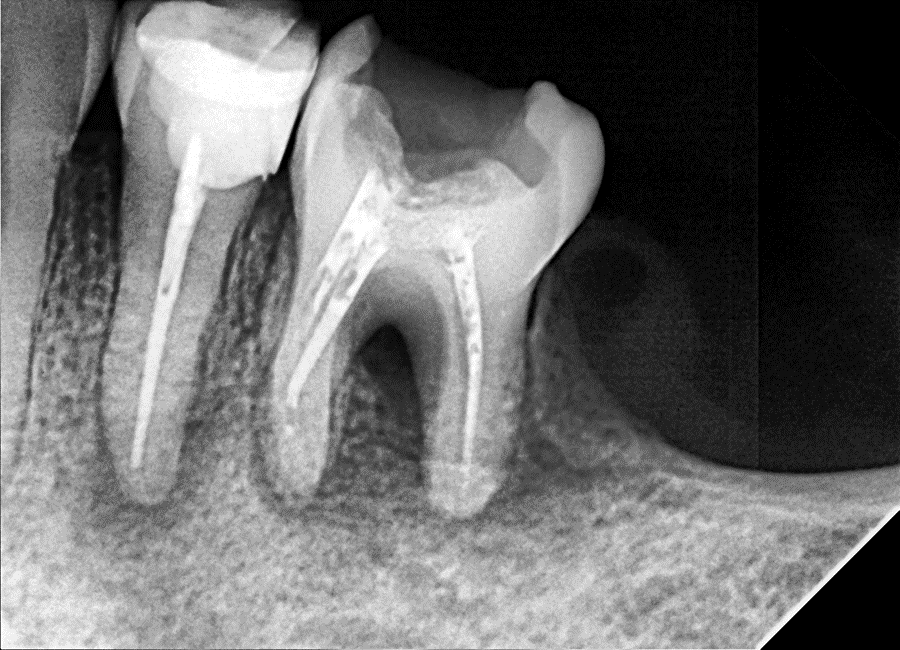

Radiographic Findings:

Large periapical radiolucency with Noticed  bone loss in the furcation area .

Figure 1. Pre-operative radiograph of tooth #36 showing extensive periapical radiolucency and complete loss of bone in the furcation area.

Figure 1